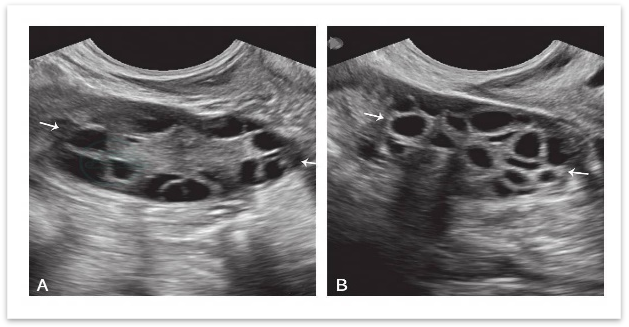

✅揪出「隐形问题」:有些情况肉眼无法察觉,比如卵泡长到一定程度却不破裂(未破裂卵泡黄素化综合征),或者卵泡没长够大小就提前排出。这些问题都会影响受孕,而动态监测能及时发现异常,为医生调整方案提供依据。

▲卵巢多囊样改变